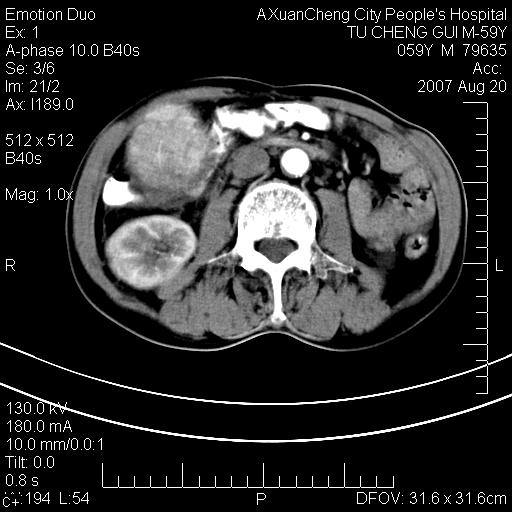

增强

巨块性肝癌!(平扫不均匀低密度,增强方式典型的快进快出)

患者有肝硬化,平扫病灶呈不均性低密度,增强呈快尽快出表现,内见更低密度灶,静脉期延迟期呈低密度符合肝癌表现,内低密度为坏死改变并少量胸腹水。

动脉期肝右动脉粗细不均,走行有点迂曲,门脉期门脉右支有点受侵,并且中心有坏死,呈快进快出,符合肝癌

典型肝癌ct表现(肝右叶肿块密度不均,增强典型快进快出,内部有液化坏死,可能有脂肪变性)。

肝右叶巨块型肝癌伴少量腹水.双侧少量胸腔积液.